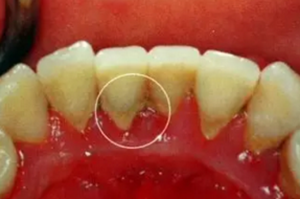

(1)齦上牙結(jié)石

位于齦緣以上的牙面上,肉眼可直接看到。在牙頸部沉積較多,特別是在大涎腺導(dǎo)管開口相對處,如上頜磨牙的頰側(cè)和下頜前牙的舌側(cè)沉積更多。齦上牙石中無機鹽的主要來源是唾液中的鈣、磷等礦物鹽。

2.png